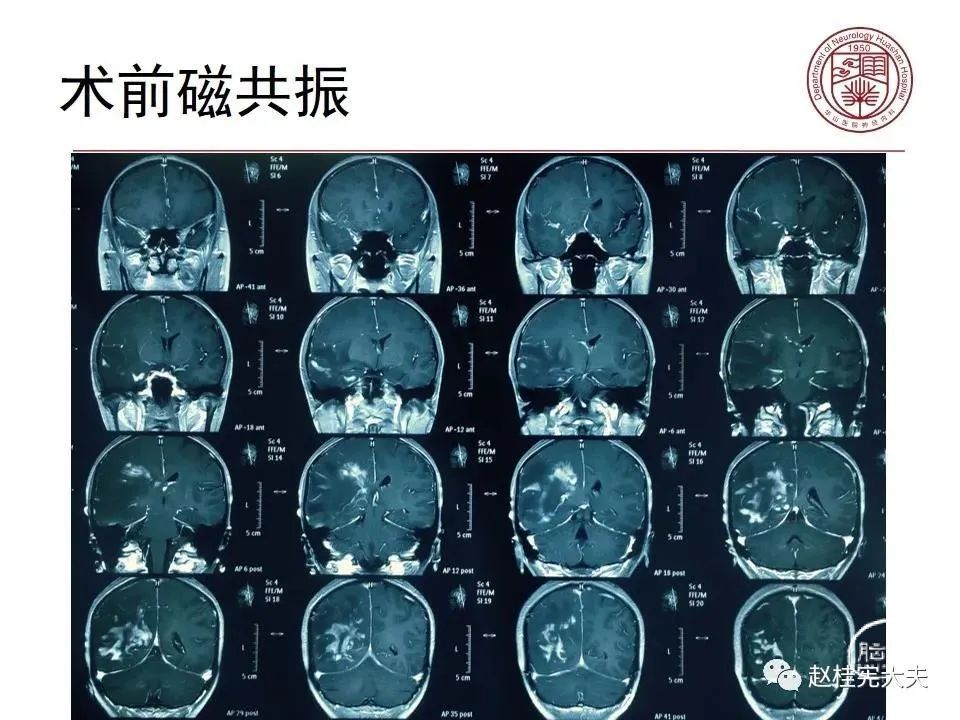

患者女性,19岁,反复头痛数年,近期加重伴记忆力下降,反复查磁共振报正常。结合病史,仔细阅片发现大脑皮层Flair、DWI异常信号。抽血查血清MOG抗体1:32,诊断MOG皮层脑炎。